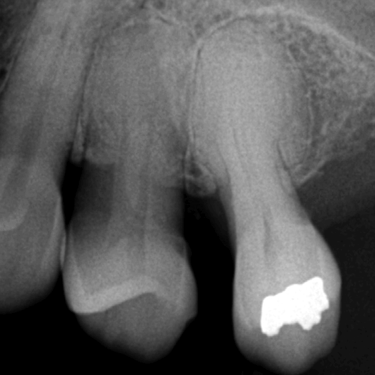

Reabsorción Interna

La reabsorción interna es la destrucción progresiva de la dentina desde el interior del diente hacia afuera, generalmente debido a un trauma o inflamación pulpar.

Los pacientes pueden notar un cambio de color en el diente.

Es necesario un tratamiento de conducto para detener el proceso y salvar el diente. Sin tratamiento, el diente puede debilitarse y fracturarse.